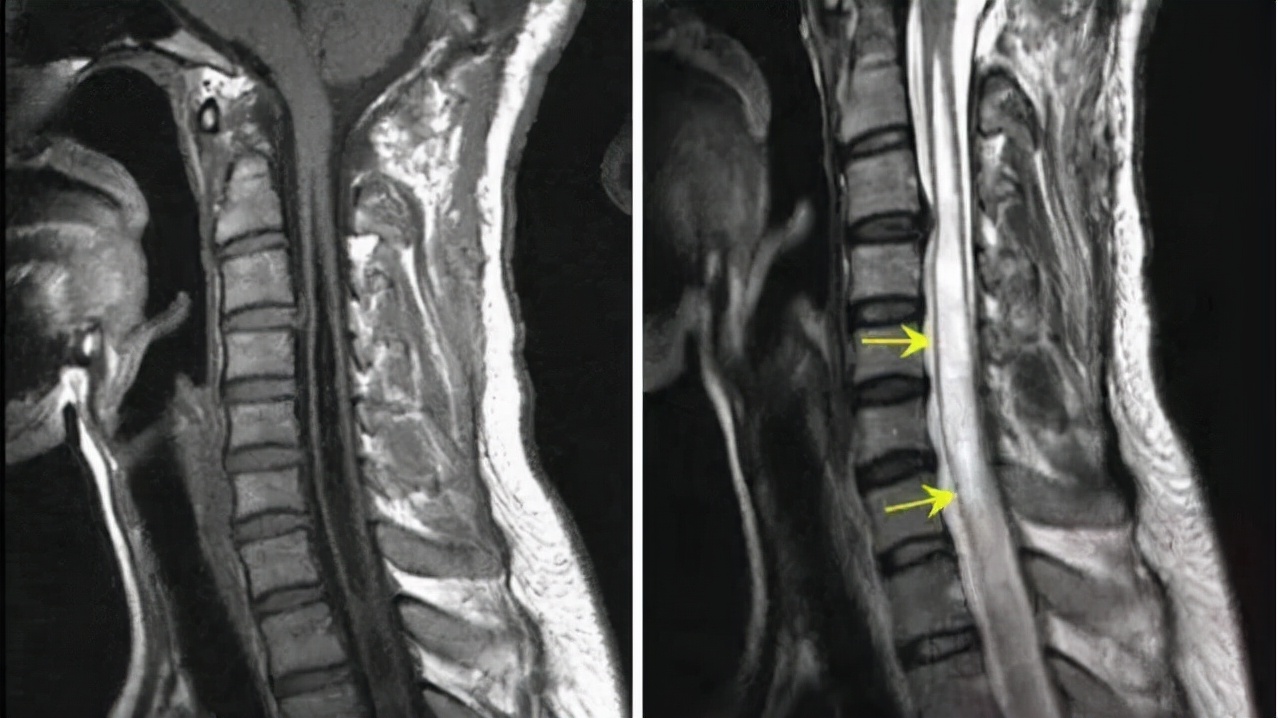

看看下面这张磁共振片子,其中圈出来的地方被我们称之为脊髓空洞,许多人对于这个称呼十分陌生,而且觉得很神秘?身体上怎么会出现空洞?甚至十分恐慌,今天我们就来讲讲关于脊髓空洞的系列问题。

之前,就有一位脊髓空洞症的男性患者,他的主要问题是寰枕融合,寰椎和枕骨长成了一体,同时伴有寰枢椎的脱位,齿状突向后移位,压迫脑干,造成了小脑扁桃体下疝以及脊髓长节段的空洞。空洞是从颈段一直到上胸段,很长。

来的时候已经痛温觉的异常、双上肢的麻木、肢体行走姿态的变化。最主要的症状就是感觉的异常、双上肢的麻木。做完手术后,效果满意。术后2周复查时,从颈段到胸段的脊髓空洞几乎已经看不见了(可以说90%~98%以上的空洞都没有了),小脑扁桃体对脑干的压迫也已经完全解除了,症状相继得到了改善。